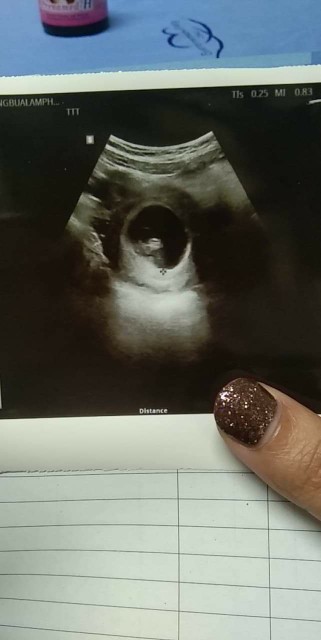

รูปตอน9วีคค่ะตอนนี้16วีคเเล้ว.😂

9w+6dซาววันนี้ค่าาา ทีมสิงหา